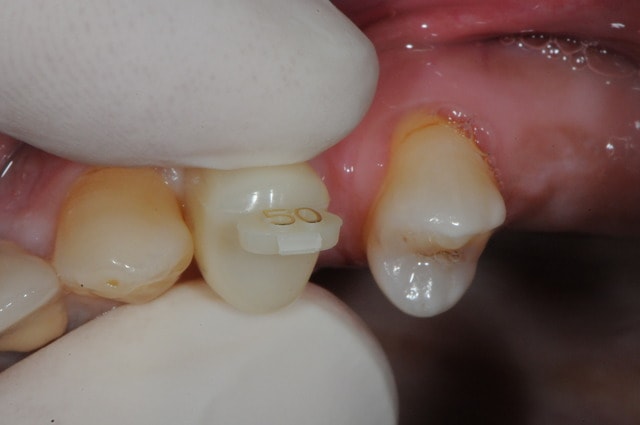

dis moi la tu le trouves comment mon compromis avec l'espace biologique

eii

d'après toi faites il y a combien de temps?

Superbe ratrapage suite à une operculisation d'une vis de couverture. Félicitations. Je te savais costaud béotien mais là tu m'impressionnes vraiment.

- pas de vis de couverture , pas d'operculisation!!

Même pas de lambeau pédiculé palatin!